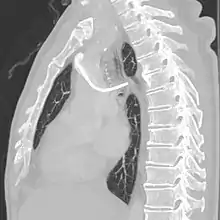

A port consists of a reservoir compartment (the portal) that has a silicone bubble for needle insertion (the septum), with an attached plastic tube (the catheter). The device is surgically inserted under the skin in the upper chest or in the arm and appears as a bump under the skin. It requires no special maintenance other than occasional flushing to keep clear. It is completely internal so swimming and bathing are not a problem. The catheter runs from the portal and is surgically inserted into a vein (usually the jugular vein or less optimally the subclavian vein). Ideally, the catheter terminates in the superior vena cava or the right atrium. This position allows infused agents to be spread throughout the body quickly and efficiently.

After the entry site is punctured with ultrasound, a guidewire is inserted with the tip of the guidewire reaching the inferior vena cava. The proximal end of the guidewire is secured to prevent dislodgement. Then a chemoport pocket is created on the deltopectoral region at 2.5 cm below the level of clavicle by using a scalpel. Bupivacaine with adrenaline (0.25%) is used as local anesthetic to reduce the formation of haematoma and prolong the anesthetic effect. After the pocket is created, a trocar is used insert a silicone catheter from the pocket towards the internal jugular vein puncture site. A peel-away sheath is then inserted to facilitate the insertion of the silicone catheter into the cavoatrial junction. Silicone catether insertion should be done during breath hold at inspiration. The peel-away sheath should be pinched to prevent air embolism. The proximal end of the catheter is connected to the port within the skin pocket later after irrigation of the pocket with normal saline.[3]

The port is then sutured on two sites to the underlying muscles. The tip of the catheter is checked for kinks and position using a fluoroscope. Besides that, aspiration of blood and contrast injection through the chemoport can also be used to confirm the position. The port is the closed in two layers (subcutaneous tissue is sutured first, followed by the skin). Sterile dressing is then placed on the port.[3] The optimum site to park the tip of the catheter is at the cavo-atrial junction or with margin of error of not more than 4 cm above the junction.[3]

The incidence of catheter fracture is 2.3%. The fracture can be due to "pinch-off syndrome" when the vein and the catheter is compressed when passes between the clavicle and first rib before turning 90 degrees into the superior vena cava. Fractured catheter component can dislodge most commonly into pulmonary arteries (35%), right atrium (27%), right ventricle (22%), and superior vena cava and peripheral veins (15.4%).[5]